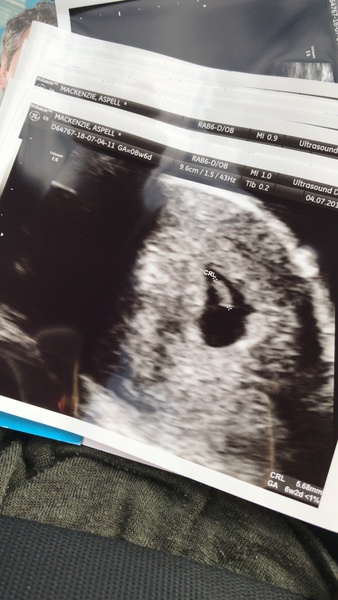

Saw my little jelly bean yesterday! Heard the heart beat and everything 😍 it’s going to be so exciting when we’re all getting 12 week scans at the same time! I’ve been put back by 2 weeks though from 9 to 7 weeks not to worried about it but was a bummer changing my dates on flow and watching him get smaller x